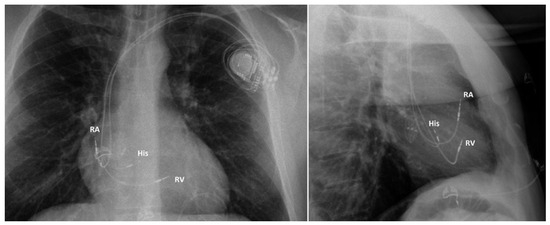

Figure 5.

Chest X-ray in a patient implanted with a pacemaker for atrioventricular block. RA: right atrial lead; His: His bundle lead (connected to the left ventricular port of the biventricular pacemaker); RV: right ventricular lead on the interventricular septum (connected to the right ventricular port of the pacemaker).